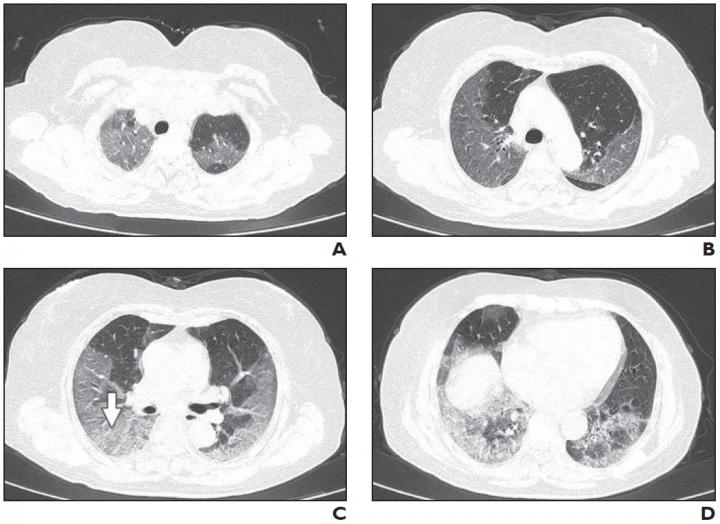

Leesburg, VA, March 3, 2020--A multi-center study (n=101) of the relationship between chest CT findings and the clinical conditions of coronavirus disease (COVID-19) pneumonia--published ahead-of-print and open-access in the American Journal of Roentgenology (AJR) --determined that most patients with COVID-19 pneumonia have ground-glass opacities (GGO) (86.1%) or mixed GGO and consolidation (64.4%) and vascular enlargement in the lesion (71.3%).

In addition, lead authors Wei Zhao, Zheng Zhong, and colleagues revealed that lesions present on CT images were more likely to have peripheral distribution (87.1%) and bilateral involvement (82.2%) and be lower lung predominant (54.5%) and multifocal (54.5%).